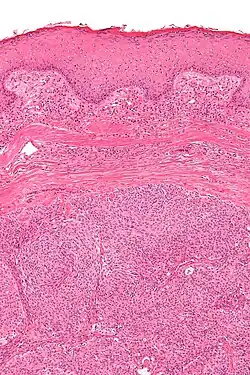

| Micrograph showing an acrospiroma. H&E stain. | |

Hidradenoma refers to a benign adnexal tumor of the apical sweat gland.[1][2] These are 1–3 cm translucent blue cystic nodules. It usually presents as a single, small skin-colored lesion, and may be considered closely related to or a variant of poromas.[3] Hidradenomas are often sub-classified based on subtle histologic differences, for example:[4]

Discussion of sweat gland tumors can be difficult and confusing due to the complex classification and redundant terminology used to describe the same tumors. For example, acrospiroma and hidradenoma are synonymous, and sometimes the term acrospiroma is used to generally describe benign sweat gland tumors. In addition, a single lesion may contain a mixture of cell-types.[2] There has also been a change in understanding about how tumors that were previously believed to strictly derive from specific sweat gland types may, in fact, derive from both eccrine or apocrine glands.[5][6]